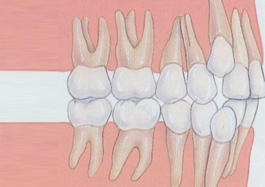

- 数字A6-隐形SGTB正畸技术以突面畸形伴颌位因素的矫形矫治为突破点,该矫治器是基于数字化技术和3D打印技术开发的新一代双牙合板矫治器,其设计要点为通过颌位重建确保前导,通过附件设计实现力学传递,通过牙合垫渐薄实现牙齿尖窝对接。

- 数字化A6隐形—SGTB正畸技术主要适用于青少年骨性错颌畸形如深覆颌、深覆盖。

- 以往骨性错颌畸形和拔除前磨牙的高疑难症状还停留在用钢丝固定矫治的阶段,如今A6、A7技术通过隐形牙套也可很好的解决这类症状,让青少年骨性功能性矫治和成人疑难错颌畸形矫治变得高效、美观、舒适。